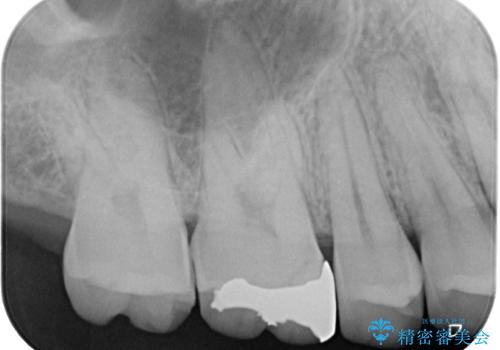

- 保険診療で治療した銀歯のやり替え希望の患者様です。

銀歯とその下の虫歯を除去し、形を整え、精度の良いシリコーンによる型どりを行いました。

精度の高い詰め物は、二次う蝕になりにくいです。